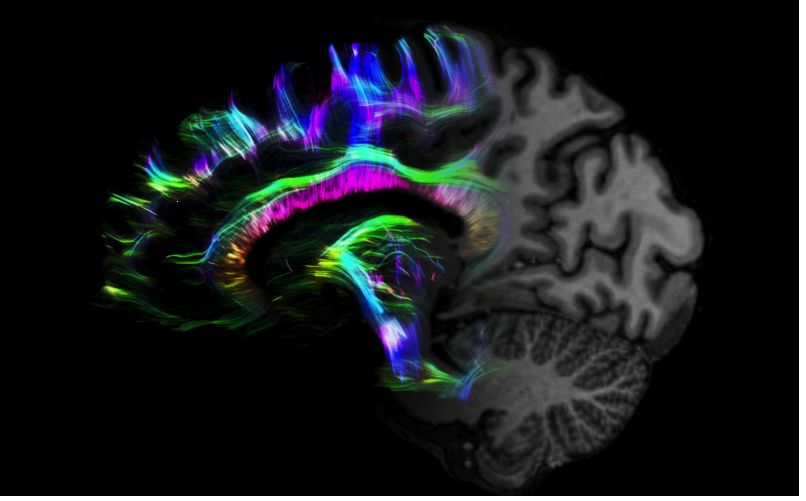

MAGNETOM Terra在業(yè)界首次實現(xiàn)了兩倍于傳統(tǒng)7T的超強梯度性能,實現(xiàn)超快速、超高效、超高分辨功能磁共振成像。如此高性能的梯度系統(tǒng)無論對于科研還是臨床都帶來了更多可能。

1毫米的各向同性分辨率DTI:神經(jīng)纖維束的交叉細節(jié)顯示